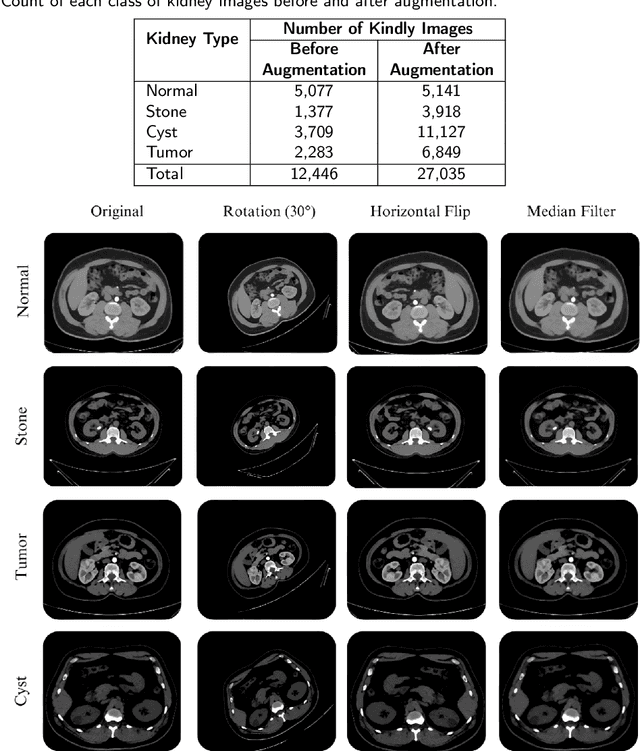

Abstract:Medical image classification is a vital research area that utilizes advanced computational techniques to improve disease diagnosis and treatment planning. Deep learning models, especially Convolutional Neural Networks (CNNs), have transformed this field by providing automated and precise analysis of complex medical images. This study introduces a hybrid deep learning model that integrates a pre-trained ResNet101 with a custom CNN to classify kidney CT images into four categories: normal, stone, cyst, and tumor. The proposed model leverages feature fusion to enhance classification accuracy, achieving 99.73% training accuracy and 100% testing accuracy. Using a dataset of 12,446 CT images and advanced feature mapping techniques, the hybrid CNN model outperforms standalone ResNet101. This architecture delivers a robust and efficient solution for automated kidney disease diagnosis, providing improved precision, recall, and reduced testing time, making it highly suitable for clinical applications.